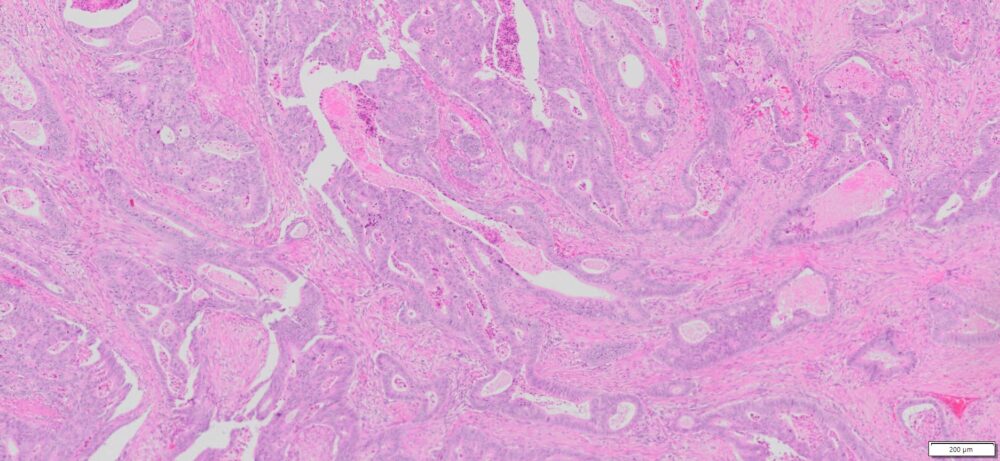

Description

| Tissue | Pathology Diagnosis | Gender/Age (year) | % Tumor area | Tumor Grade | TMN Stage | IHC Data |

| HumanRectum | Moderately differentiated adenocarcinoma of the Rectuma | Female/59 | 45% | II | pT3pN1bpMx | MLH-1,MSH-2,MSH-6 and PMS-2: Preserved nuclear Staining |

Images for H&E Stain and IHC